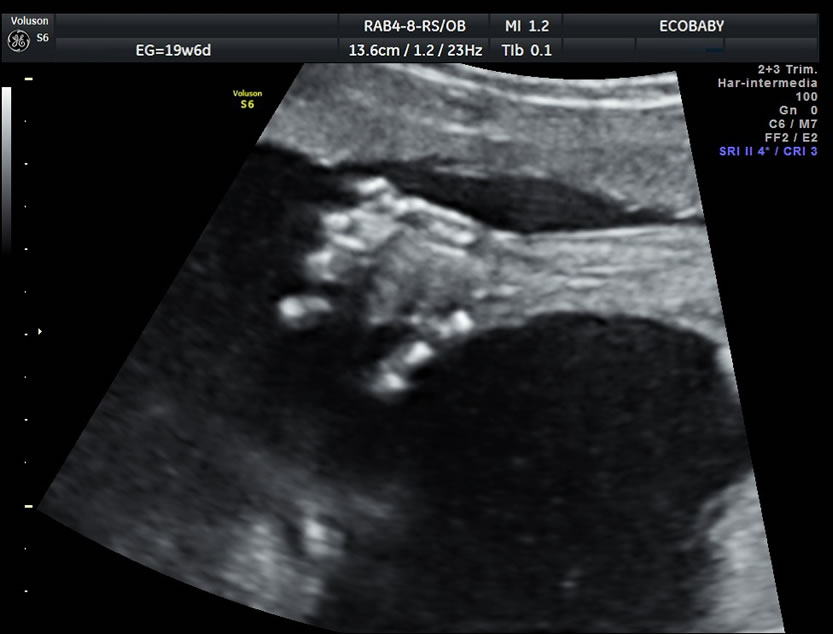

Cerebro, cuello, cara, tórax, corazón (diferentes cortes que muestran las cavidades y la correcta entrada y salida de arterias y venas), abdomen (normalidad de la pared, estómago, intestino, riñones, vejiga), miembros inferiores y superiores y columna vertebral.